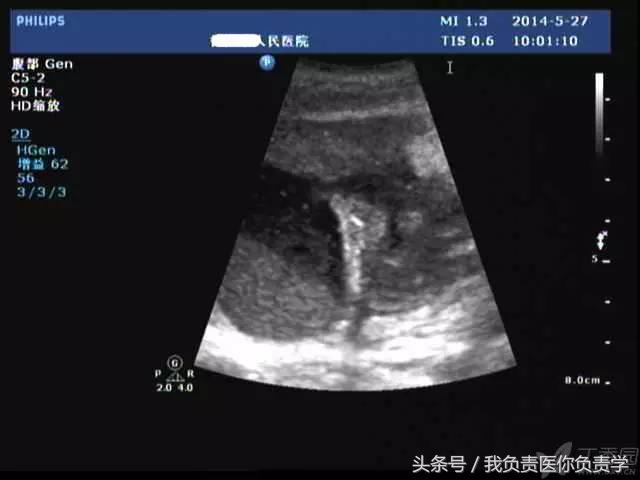

典型病例 2

(由丁香园注册用户「chengxiuyan_123」提供)

患者女,68岁,因上腹部痛 8天就诊 。超声检查发现胆囊体积明显增大,内部透声差,囊壁明显增厚,胆囊周围可见不规则分布的液性暗区。胆囊壁局部回声中断,探头加压及松开时,CDFI可见中断处出现因液体进出胆囊而导致的多普勒信号。患者行胆囊切除术,术后证实为胆囊穿孔。

图1示胆囊体积明显增大,内部透声差

图2示胆囊周围可见液性暗区分布

图3-图6示胆囊壁局部回声中断,探头加压及松开时CDFI可见红色及蓝色多普勒信号